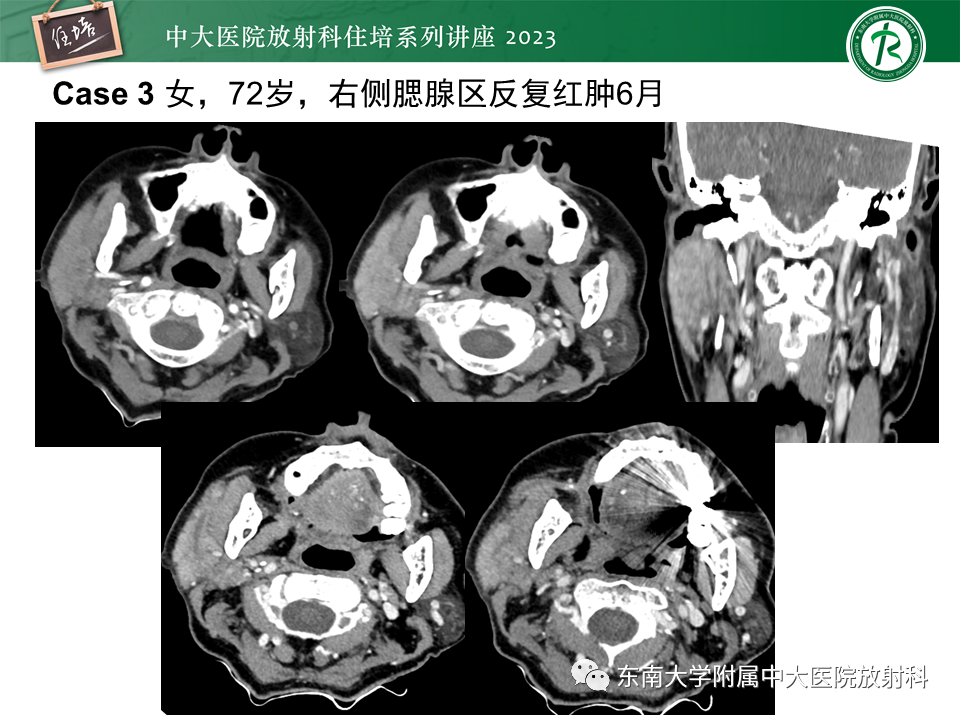

腮腺病变影像表现及诊断思路